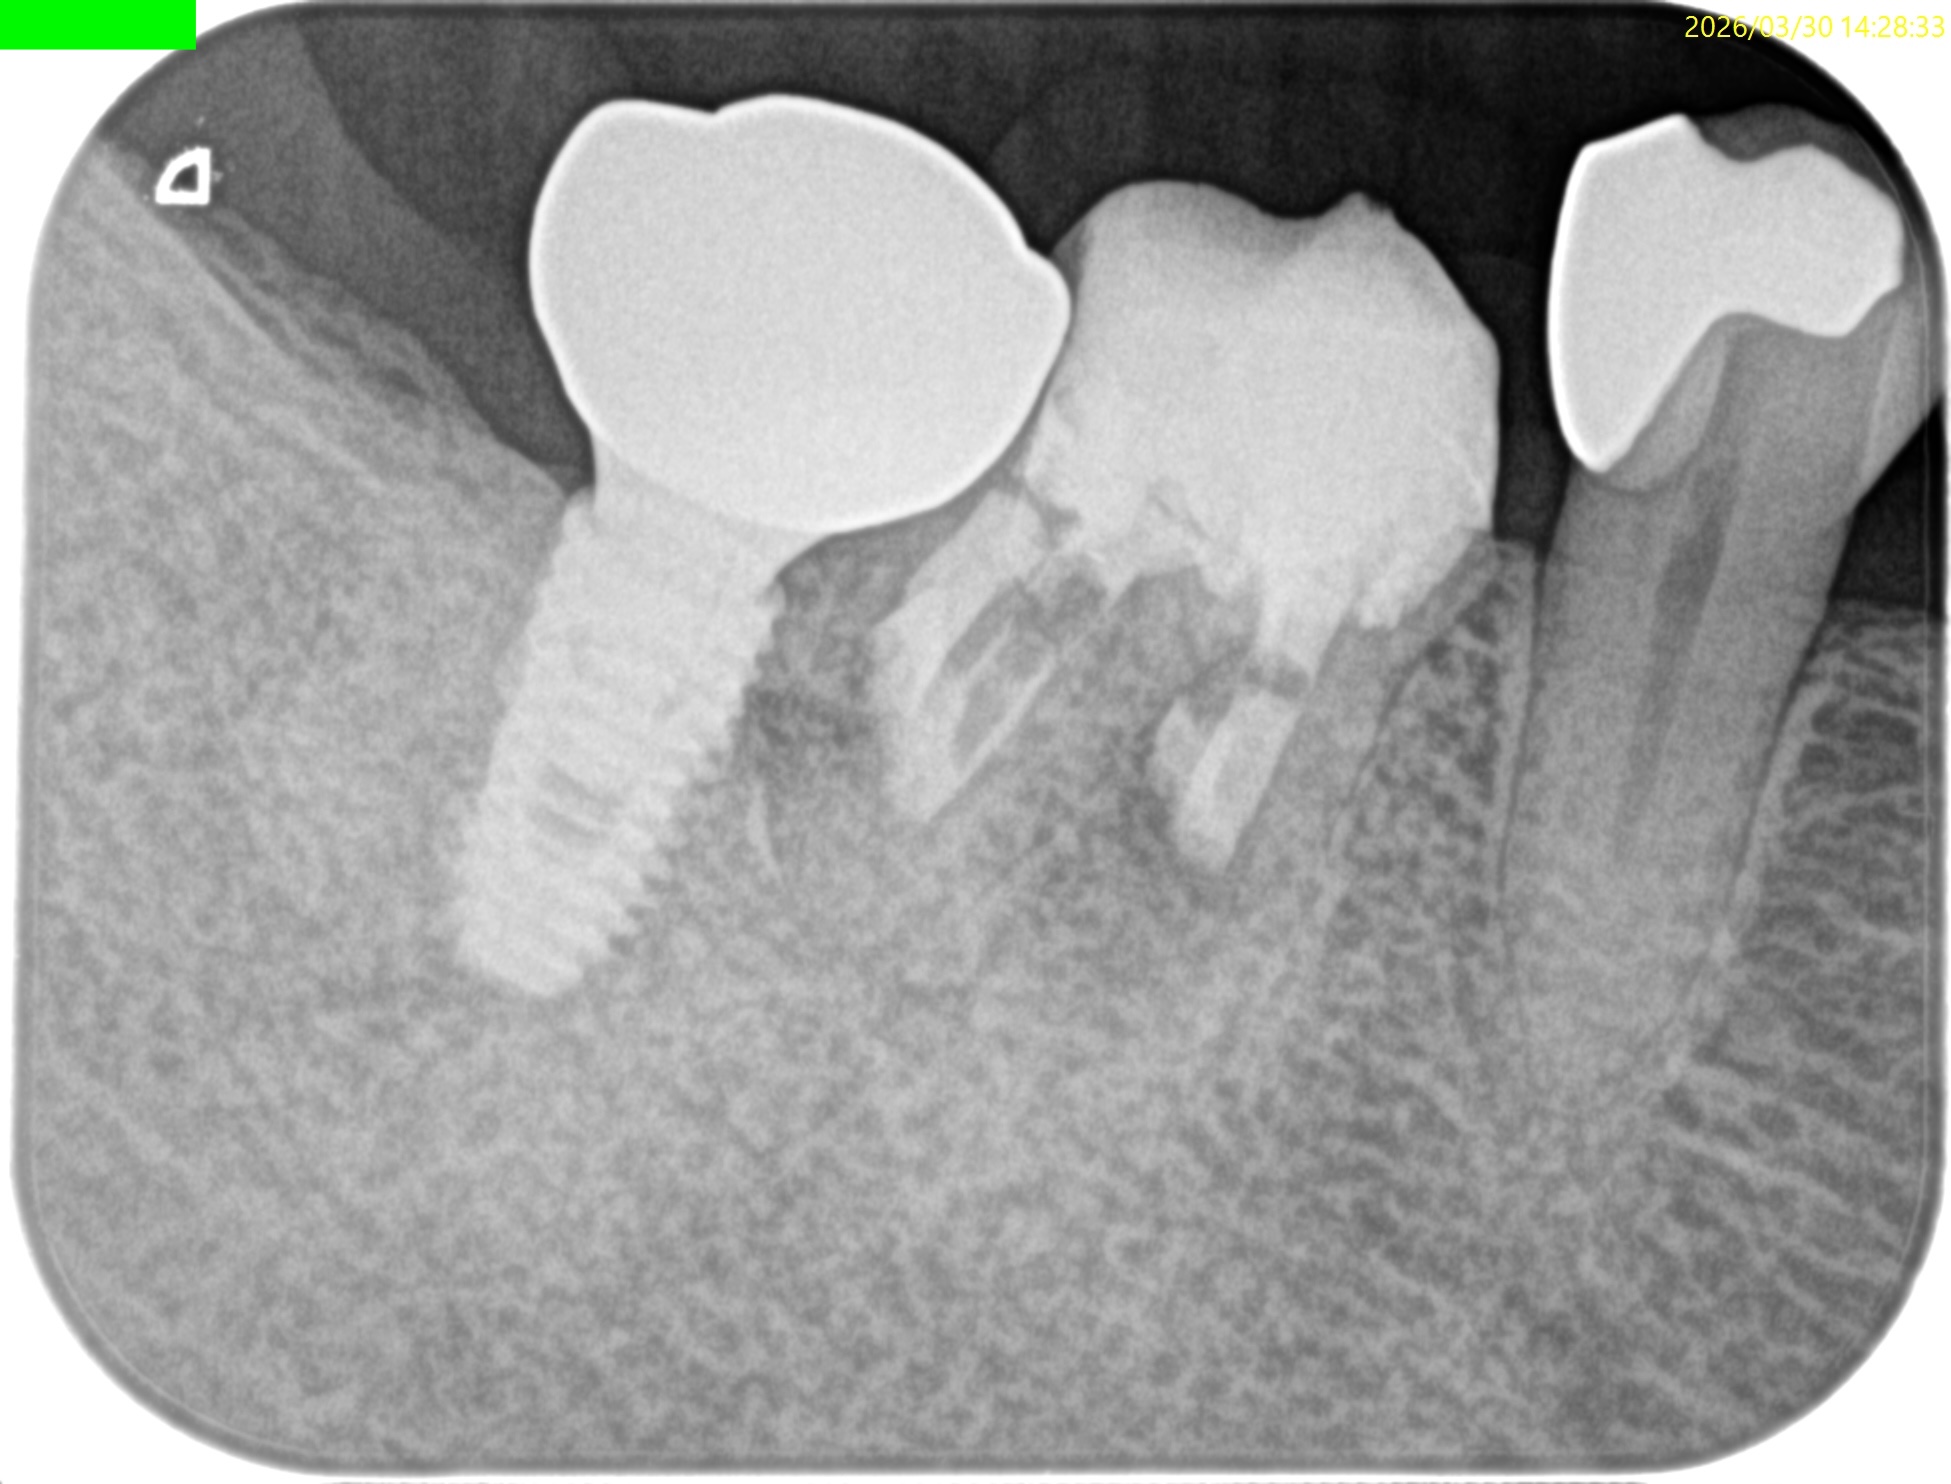

#30 M,D Apicoectomy 5M recall(2026.3.30)

D

外科直後と比較した。

最終補綴もOKだ。